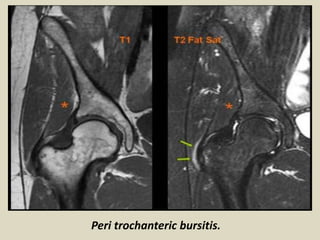

Peri trochanteric bursitis.